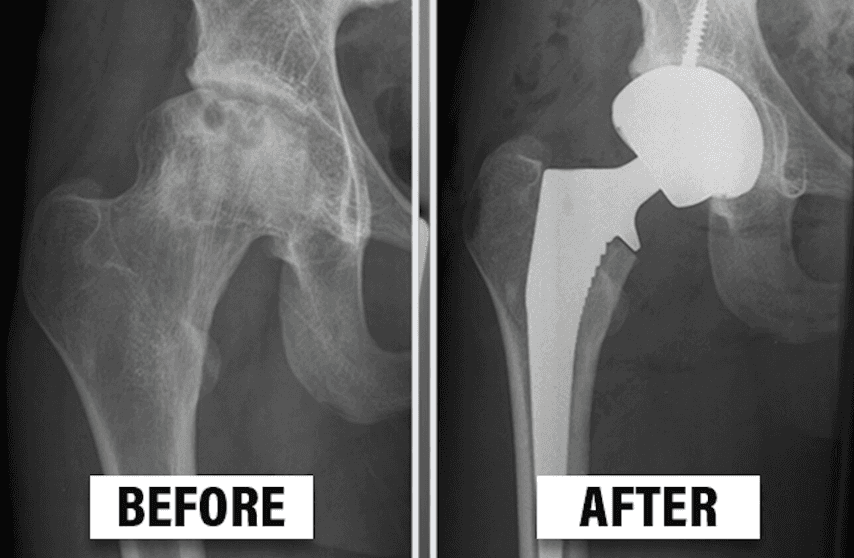

What is hip replacement surgery

Hip Joint replacement involves removing the damaged parts of the hip joint and replacing them with artificial components, known as prostheses.

Traditional Total Hip Replacement (THR) Surgery

A traditional hip replacement surgery involves a large incision, generally 10 to 12 inches that enables surgeons to access the diseased hip joint.

The main drawbacks of a traditional hip replacement surgery are longer incision, cutting of the important muscles to access the hip joint, more blood loss, many lifestyle restrictions & longer recovery time. This makes the post-operative period more painful and the surgical wound takes longer time to heal as well. Patients are generally not allowed to squat or sit cross legged on the floor after a conventional hip replacement surgery. Longer recovery period also means late return to work, which in turn adds to the financial burden of the patient & it can be counted as increased cost of the surgery, as the patient could have earned during that period if he had returned to work earlier.

Direct anterior approach(DAA) total hip replacement is surgical procedures performed through small incisions, often guided by specialized instruments and advanced imaging technology,with aim to minimise trauma to surrounding tissues, reduce blood loss, and accelerate recovery times with very minimal pain even in the early post-operative period of the surgery for patients such that the new hip joint feels near normal after the surgery & most of the patients forget in due course of time that they ever had any hip surgery.